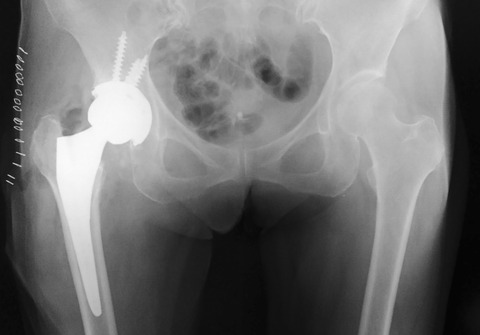

先日、大腿骨頚部骨折後偽関節に対する人工股関節全置換術(THA)がありました。まだ60歳台ですが、既に寛骨臼側にOAも認められたため他院から紹介されました。

人工骨頭置換術でお茶を濁す手も無きにしも非ずですが、年齢が若いことと今後の活動性を考えて、セオリー通りにTHAを施行することにしました。

しかし、この手の症例は、骨質が極端に悪いことが多いので要注意です。私は基本的にセメントレス派ですが、念のためセメントTHAもバックアップして手術に臨みました。

案の定、骨質が非常に不良で、寛骨臼のリーミングもほんの数秒で内板まで到達してしまいました。軟骨下骨をある程度温存するつもりでしたが、感覚が分かりませんでした。

大腿骨も骨質不良でしたが、一応セメントレスステムでラスピングしてみました。意外とプレスフィットしたので、そのままセメントレスステムで終了しました。

終わってみると、意外にも寛骨臼・大腿骨側ともセメントレスでしのぐことができました。あ~、よかった。カチカチのOAと比べると、このような症例は非常に緊張します。